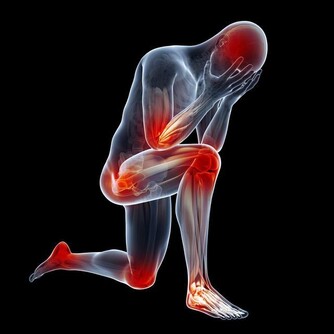

痛風,幾乎也是讓大家聞之色變的一類疾病了,因為一旦患上了痛風,不僅身體會長時間受到折磨,精神上也會感到十分痛苦,而且在痛風患者的日常生活中,稍有不慎就可能會導致其他病症一齊發作。

所以,對於痛風,大家一定要有相關的防範意識,不要等到疾病纏身了,才知道後悔,尤其是平時在飲食中經常攝入高嘌呤食物,且尿酸水平持續偏高的人,更是要注意預防。